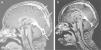

The patient had normal blood pressure; however, bilateral papilledema was detected. Magnetic resonance imaging (MRI) showed hyperintense thrombosis in the superior sagittal sinus and in both proximal segments of transverse sinuses (Fig. 1a). Subcutaneous low-molecular-weight heparin (LMWH) was started. The patient was investigated for a prothrombotic state and a methylenetetrahydrofolate reductase (MTHFR) heterozygous mutation was found. Azathioprine was added. One month later bilateral papilledema was detected again. The brain MRI was repeated and a new thrombosis distal to the superior sagittal sinus was detected. After permission from the ministry of health, infliximab was used at a 5mg/kg/day dose and 3 doses were applied on the 0, 2 and 6 weeks. Before the infliximab, azathioprine was stopped; prednisolone was tapered and stopped at the 7th day of infliximab. Ten days after first dose of infliximab, C-reactive protein was decreased to normal range, and both frequency and severity of the oral aphthous lesions were reduced. Resolution of the thrombosis was seen after the second dose of infliximab in the brain MRI (Fig. 1b). Ongoing therapies consist of colchicine and LMWH. Infliximab was well tolerated by this patient; no drug-induced side effects were recorded.

(a) Magnetic resonance imaging of brain before the infliximab. Hyperintense thrombosis filling the superior sagittal sinus and proximal segments of both transverse sinuses was showed and (b) after second dose of infliximab, significant dissolution of the thrombosis was observed in the brain MRI.